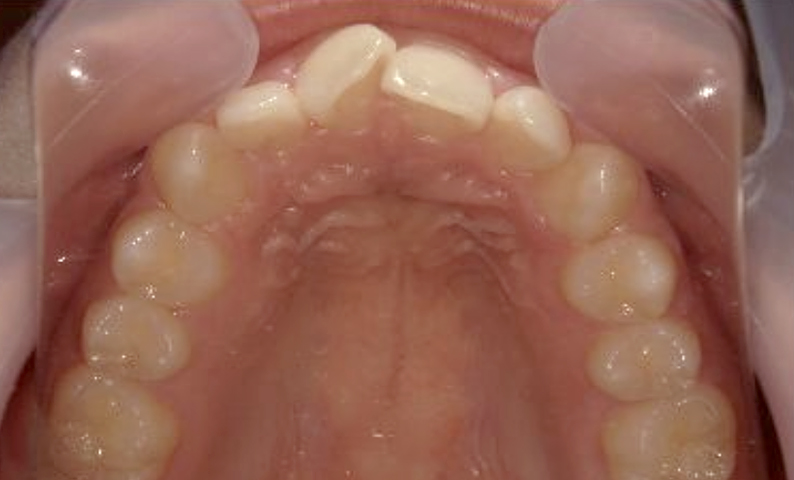

症例_004 上下顎の部分矯正

治療期間:8ヶ月金額:54万円+税女性前歯のガタガタ捻転歯

| Before | After |